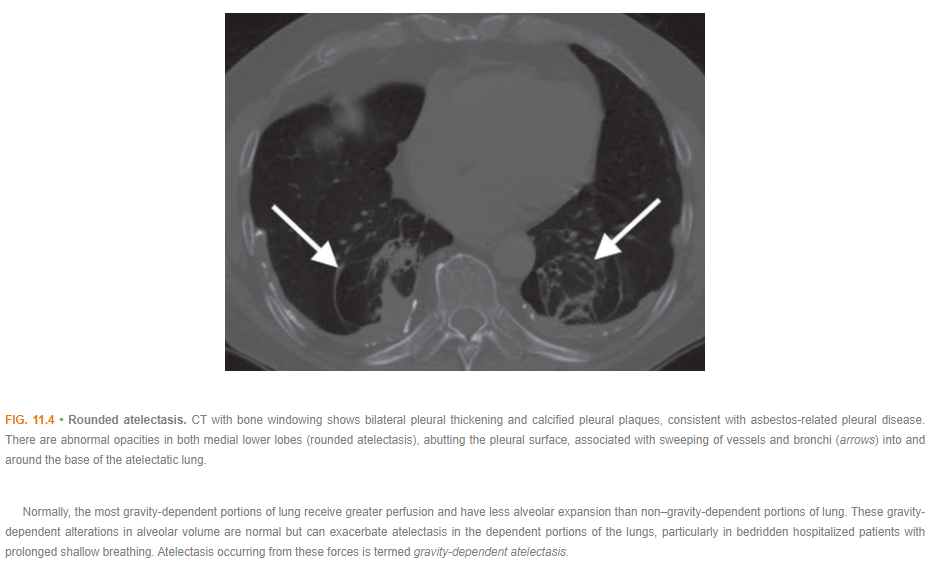

Atelectasis>